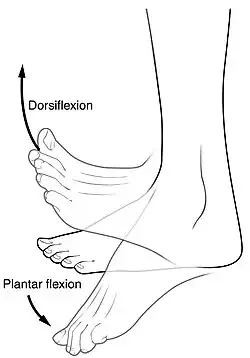

A dor característica da fascite plantar é geralmente sentida na parte de trás do calcanhar e é mais intensa durante os primeiros passos do dia.[7] Indivíduos com fascite plantar frequentemente apresentam dificuldade para realizar a dorsiflexão do pé, o movimento de elevar o pé em direção à canela.[7] Esta dificuldade geralmente se deve ao retesamento do músculo da panturrilha ou do tendão de Aquiles, que é conectado à fáscia plantar.[9] A maior parte dos casos de fascite plantar melhora com o tempo e responde bem aos métodos de tratamento conservador.[7][10]

Geralmente, a fascite plantar é diagnosticada pelo clínico após a consideração da história, dos fatores de risco e do exame físico.[7][16][17] Sensibilidade à palpação da parte interna do osso do calcanhar na sola do pé pode ser observada durante o exame físico.[7][11] O pé pode apresentar dorsiflexão limitada devido ao enrijecimento dos músculos da panturrilha ou do tendão de Aquiles.[10] A dorsiflexão do pé pode ser dolorosa devido ao alongamento da fáscia plantar por esse movimento.[7][13] Estudos de imagem para o diagnóstico da fascite plantar raramente são necessários.[10] Entretanto, em alguns casos o médico pode decidir por solicitar estudos de imagem (como radiografia, ultrassonografia ou ressonância magnética), justificáveis para excluir causas graves de dor no pé. Outros diagnósticos tipicamente considerados são fraturas, tumores ou doenças sistêmicas, caso a fascite plantar não responda adequadamente ao tratamento médico conservador.[7][11] Dor no calcanhar bilateral ou dor no calcanhar no contexto de uma doença sistêmica podem indicar a necessidade de uma investigação diagnóstica mais aprofundada. Testes diagnósticos como hemograma completo ou marcadores sorológicos de inflamação, infecção ou doença autoimune, como proteína c-reativa, velocidade de hemossedimentação, anticorpo antinuclear, fator reumatoide, HLA-B27, ácido úrico ou anticorpos da doença de Lyme podem ser solicitados.[8] Déficits neurológicos devem lembrar uma investigação com eletromiografia para avaliar o dano aos músculos e nervos.[13]